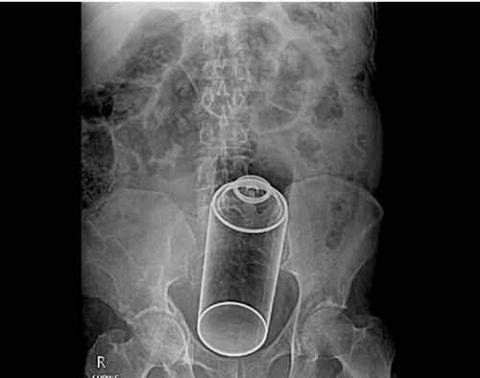

这是儿童用的玻璃杯,也能塞里面